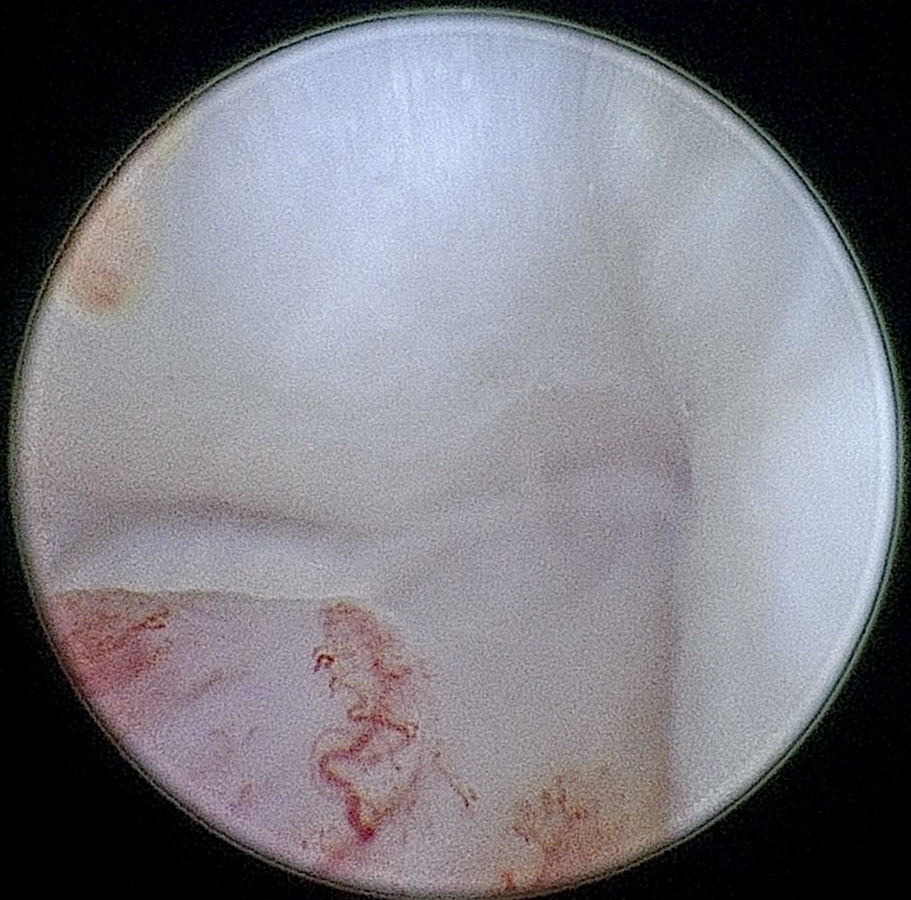

이도 내시경은 외이도부터 고막, 중이를 거쳐 내부를 고해상도로 관찰해 만성 외이염·이물·종양·고막 손상을 평가하고 세척, 조직검사까지 가능합니다.

이도 이물 제거 예시 이미지

이도이물제거